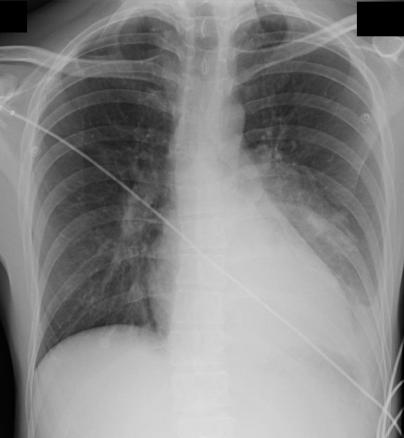

Pneumopathie base gauche

Radiographie thoracique.